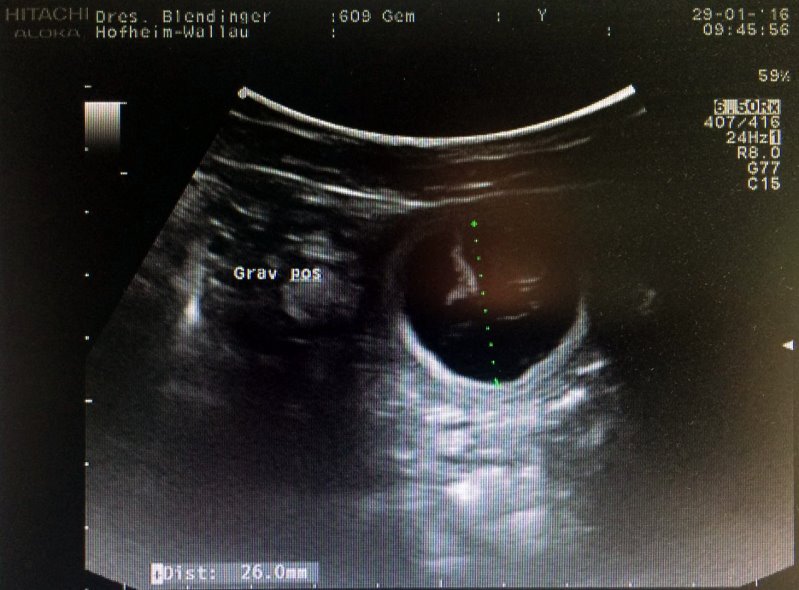

31.01.2016 - E-Wurf ist in Arbeit...

"Gemfire the Flying Eagle" ist laut Ultraschall tragend...